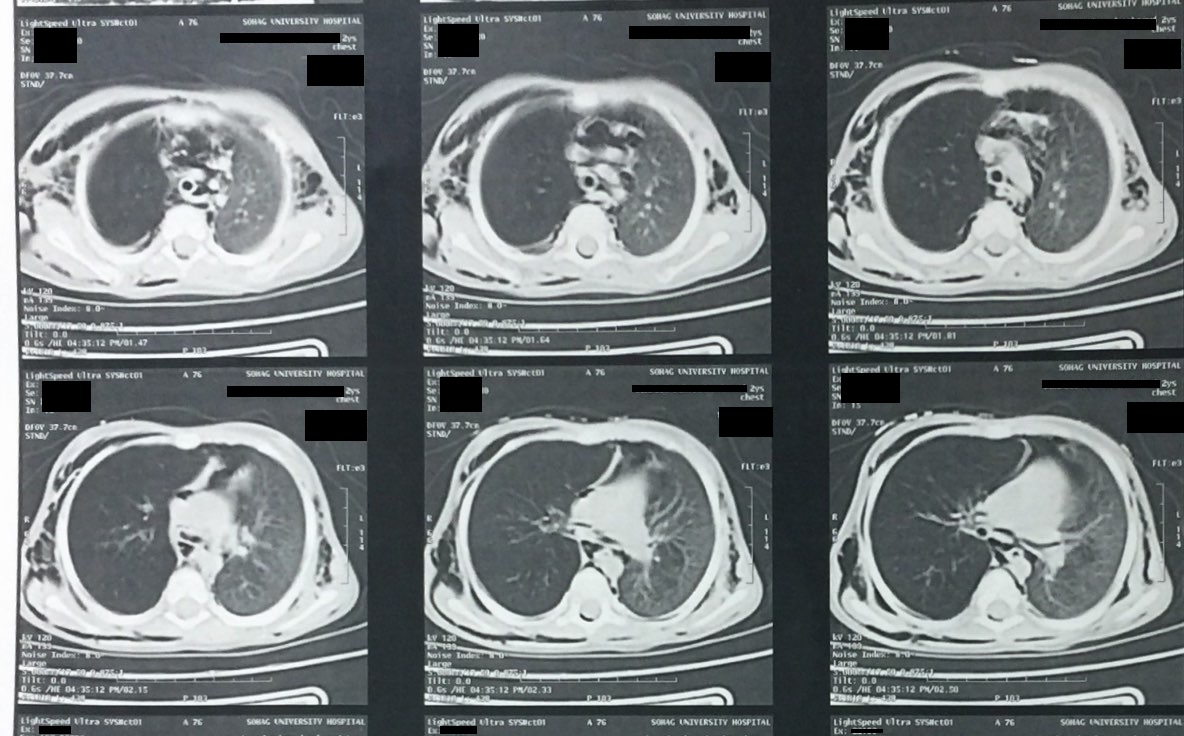

A chest x-ray (Figure 1) and computed tomography scan of the chest (Figure 2) revealed hyperinflation of the right lung, subcutaneous emphysema, and pneumomediastinum.